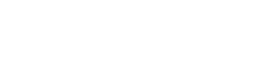

Uma mulher sofreu uma tentativa de feminicídio na manhã desta segunda-feira (2) em São Carlos, no Oeste de Santa Catarina, ao ser atacada pelo companheiro dentro da residência do casal. O agressor desferiu um golpe de faca no rosto da vítima, atingindo o olho direito, mas o crime não se consumou, segundo a polícia, graças ao pronto atendimento médico.

Conforme apurado pela Polícia Civil, o suspeito agiu com a intenção de a matar. A vítima conseguiu escapar parcialmente da agressão, mas foi atingida enquanto tentava fugir. Ela recebeu atendimento de emergência e passa por acompanhamento médico.